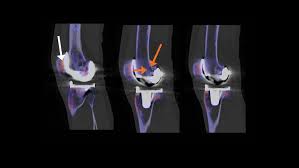

Medial Femoral Condyle, Spect Ct Delineation Of Patellar And Femorotibial Overload After Knee Arthroplasty - Please see our knee injury protocol for additional information on this topic.

Medial Femoral Condyle, Spect Ct Delineation Of Patellar And Femorotibial Overload After Knee Arthroplasty - Please see our knee injury protocol for additional information on this topic.. An articular cartilage injury, or chondral injury, may occur as a result of a pivot or twist on a bent knee, similar to the motion that can cause a meniscus tear. Osteonecrosis of the medial femoral condyle presents as a sudden onset of pain on the medial side of the knee. Osteonecrosis of the medial femoral condyle can be treated in a variety of ways depending on the stage of the disease. The femoral condyle allograft has been used for resurfacing cartilage defects with mature hyaline cartilage for several decades, with very high success rates. Your knee mri will often show a: